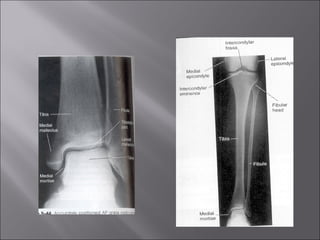

 Lateral foot, ankle, lowerleg and femur radiograph: as if they are hanging from the hip.

Toe and APand oblique foot radiographs: as if the patient is hanging from toes.